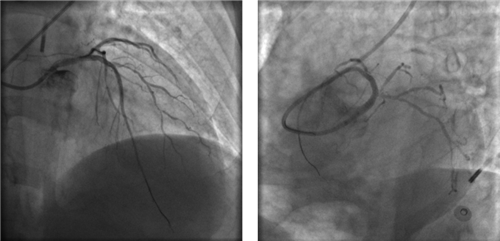

左主干完全閉塞

小心操作導(dǎo)絲及導(dǎo)管,艱難到達(dá)主動(dòng)脈根部,但導(dǎo)管難以“到位”左冠口,“冒煙”見(jiàn)左主干居然完全閉塞了。

右冠近段嚴(yán)重狹窄,未見(jiàn)右向左的側(cè)枝循環(huán)

再行右冠造影,右冠近段也嚴(yán)重狹窄,未見(jiàn)右冠向左冠的側(cè)枝循環(huán)。

球囊擴(kuò)張后,左冠血流恢復(fù),但左主干末端重度狹窄

左冠血流保持通暢

確認(rèn)左冠血流保持通暢,大家懸著的心才稍稍放下。

植入3枚支架,血流恢復(fù)通暢